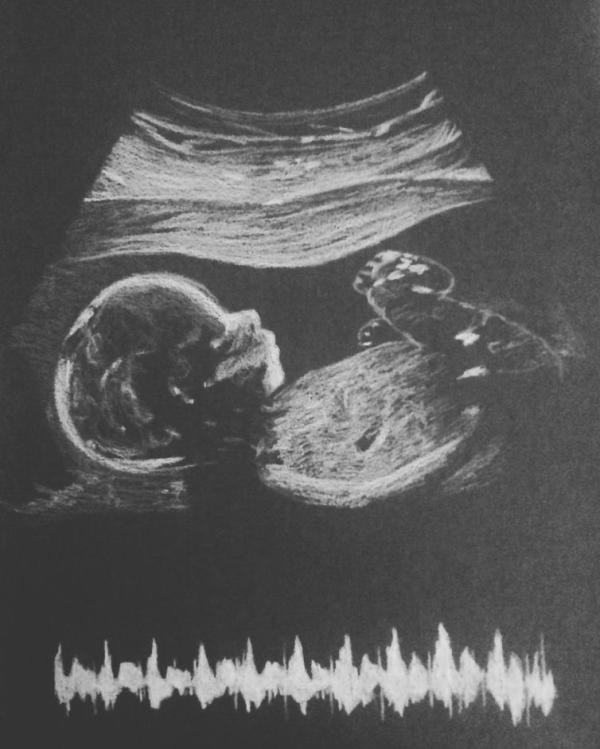

На УЗИ была пару дней назад, по фетометрии мелкий на 25 недель (по голове, ножкам и прочим замерам - в срок, а животик маленький), маловодия нет, плацента по передней, кровоток в пуповине отличный.